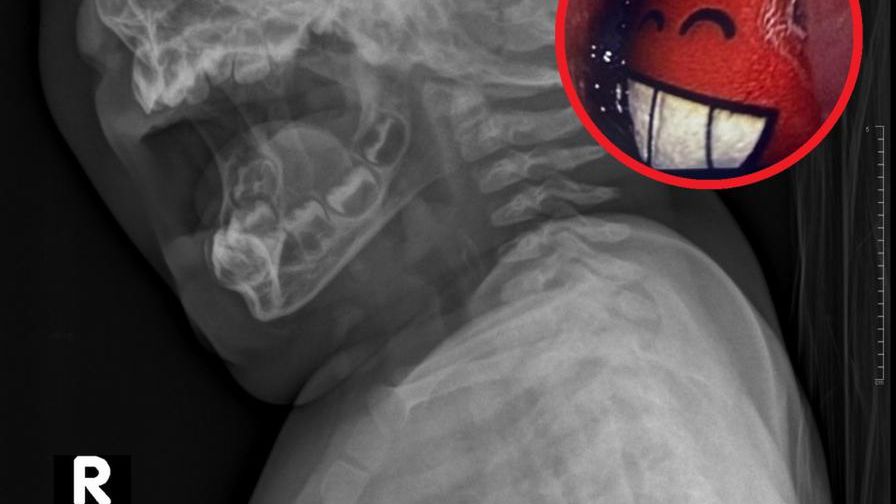

Niemowlę jest pobudzone, wymiotuje, ma ślinotok i nie chce przyjmować płynów. Badanie RTG., które wykonują lekarze, niczego nie wykazuje. Personel szpitala podejmuje więc decyzję o wykonaniu badania endoskopowego. To właśnie wtedy lekarzom ukazuje się niecodzienny widok.

Podczas gastroskopii lekarze zauważają uśmiech - i to nie byle jaki, ale szeroki, ukazujący śnieżnobiałe zęby. Na początku przecierają oczy ze zdumienia. Jednak po chwili dociera do nich to, co się stało. Dziecko połknęło naklejkę, która jest w kształcie uśmiechniętej gwiazdki i to ona zostaje uwidoczniona na ekranie podczas badania.